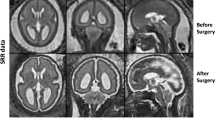

Cerebral MRI data were collected from 21 children with a complex congenital heart disease (CHD) before Fontan procedure, at a median age of 27 months (range 20.9–42.4 months). Data were segmented with SPM, FSL, and FreeSurfer, and total intracranial volume (ICV) and total brain volume (TBV) were compared with corresponding measures obtained using the Cavalieri method.

FreeSurfer provides an accurate method for measuring brain volumes in young children, even in the presence of structural brain abnormalities.